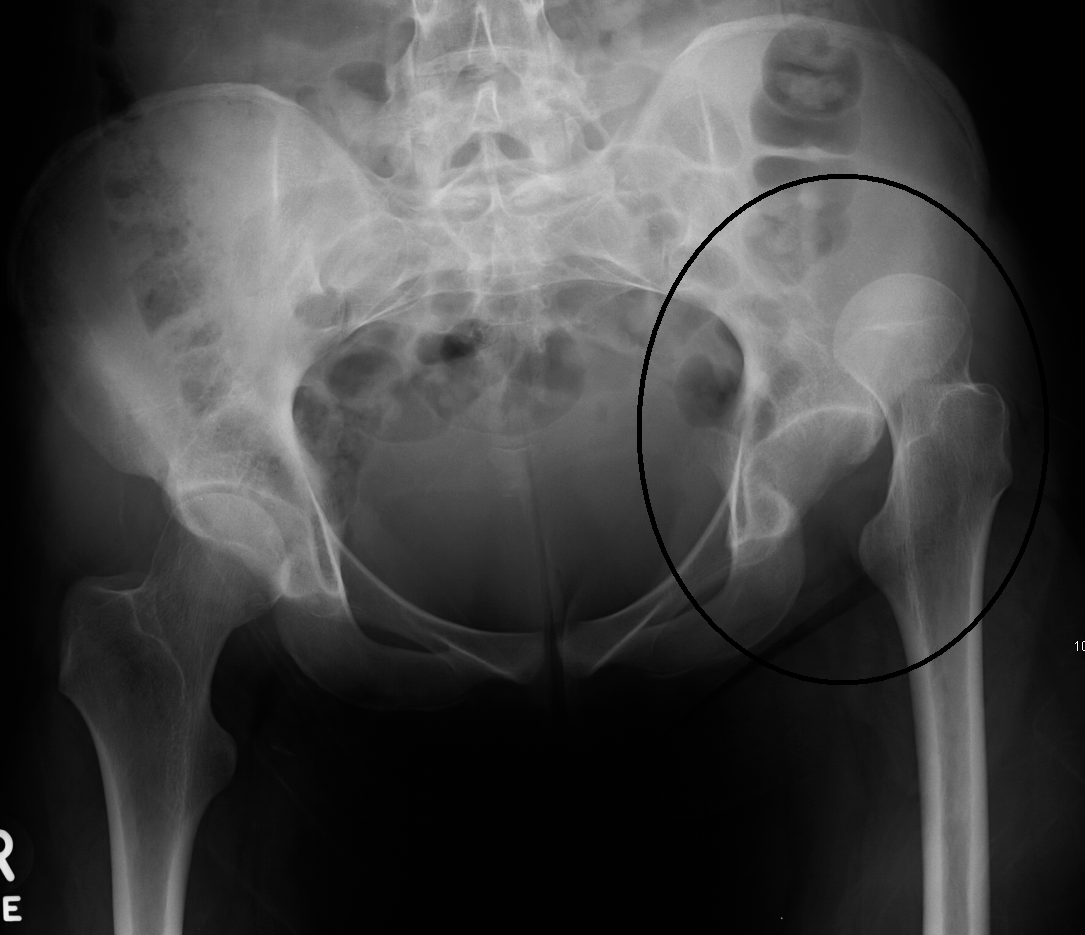

Chụp X quang

• Cần chụp X quang xương chậu và khớp háng ở tư thế thẳng. Nếu ở hõm khớp có một bất thường nhỏ chụp tia chếch 450 ra sau vào trong để phát hiện mảnh vỡ phía sau hõm khớp.